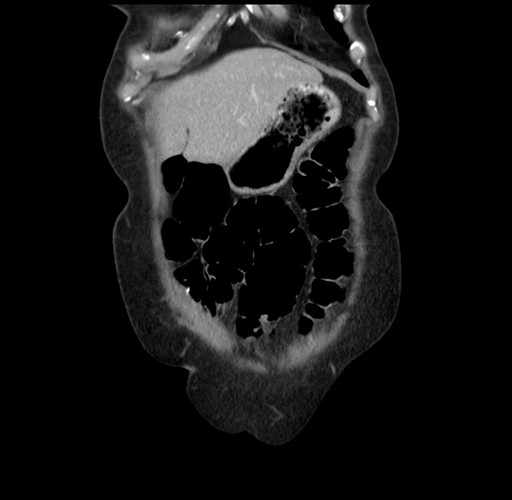

Pre-Chemo: Coronal Venous

Coronal Venous